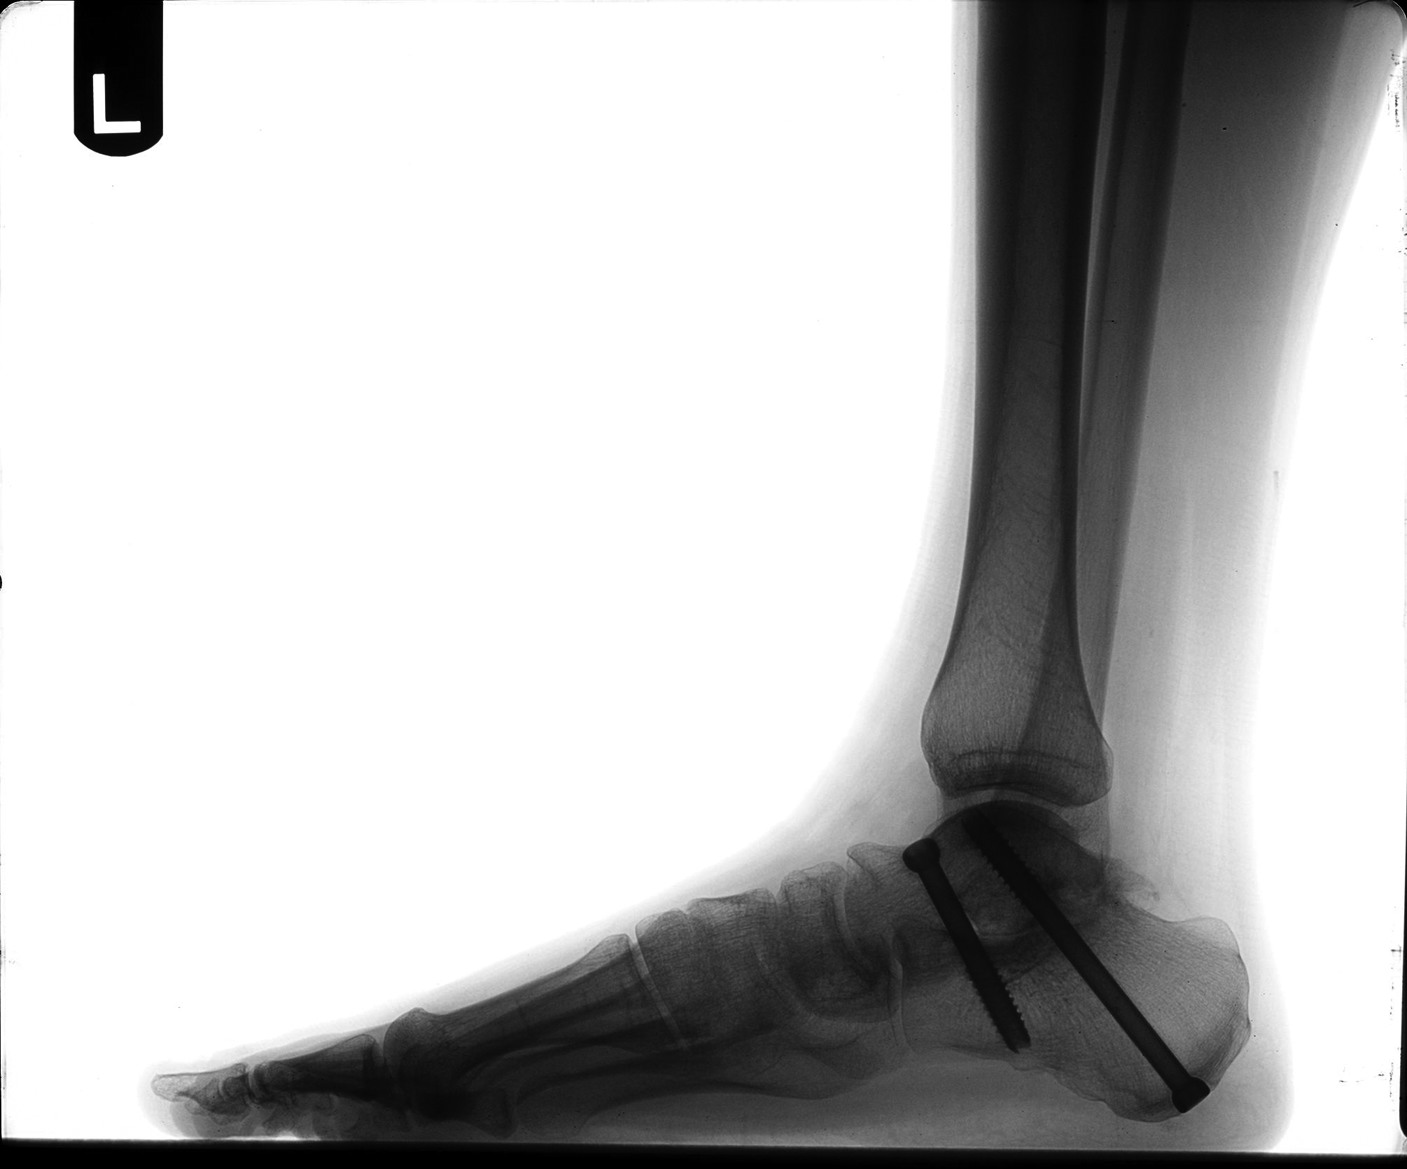

There are many surgical techniques for the treatment of tibialis posterior dysfunction due to an unstable subtalar joint. We prefer combining osseous and soft tissue procedures to correct the problem. Over the last six years, we have utilized the calcaneal Scarf to correct the rearfoot/subtalar position. The calcaneal Scarf allows accurate medial translation of the calcaneus while lengthening it in one osteotomy. The orientation of the osteotomy has increased stability over other calcaneal osteotomy options, allowing for ease of fixation and an earlier return to weightbearing. One benefit of this procedure is that it positions the subtalar joint from a valgus position into a more rectus alignment, thus reducing instability of the subtalar joint. This procedure also facilitates correction of transverse plane deformities. In the instance of severe instability that is not completely reduced by the calcaneal Scarf, we will augment our correction with an absorbable arthroereisis to further stabilize subtalar joint motion. & Correcting the weakened or absent tibialis posterior tendon is another crucial element to successful surgical outcomes. Podiatric surgeons commonly utilize a tendon transfer (flexor digitorum longus) or a tenodesis with the Cobb procedure (tibialis anterior). We prefer the Cobb procedure. However, in scenarios when one can avoid performing a tendon transfer, it is our preference to utilize the OrthoAdapt collagen scaffold (Pegasus Biologics). This material allows for reconstruction of the tibialis posterior tendon without sacrifice or insult to another tendon. With its cross-linked nature, the Orthoadapt is strong enough to maintain the correction. Its inherent collagen matrix also allows tissue in-growth, which ultimately will transition into normal host tendon tissue. In the most severe and longstanding cases of subtalar joint instability, arthritis of the subtalar joint may result. When bracing techniques fail in these situations, joint destructive procedures become an alternative. Studies have shown that surgeons can reduce 70 percent of subtalar joint motion by fusing the talonavicular joint. However, we prefer directly addressing the subtalar joint via an arthrodesis. & Arthrodesis of the subtalar joint will allow complete stability of the subtalar component of the rearfoot complex and positioning of the subtalar joint in optimal alignment. While fusion is never the preferred approach to any joint, it becomes necessary in many cases and can often lead to superior outcomes.